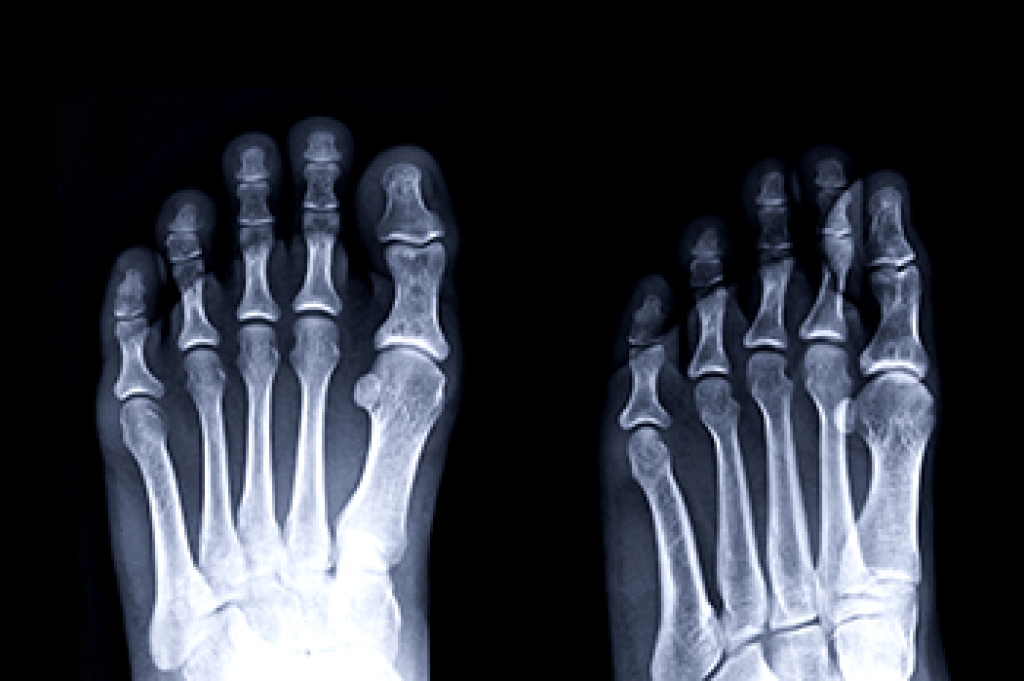

To figure out the cause of foot pain, podiatrists utilize several different methods. This can range from simple visual inspections and sensation tests to X-rays and MRI scans. Prior medical history, family medical history, and any recent physical traumatic events will all be taken into consideration for a proper diagnosis.

Diagnosis of cuboid syndrome is often difficult, and it is often misdiagnosed. X-rays, MRIs and CT scans often fail to properly show the cuboid subluxation. Although there isn’t a specific test used to diagnose cuboid syndrome, your podiatrist will usually check if pain is felt while pressing firmly on the cuboid bone of your foot.